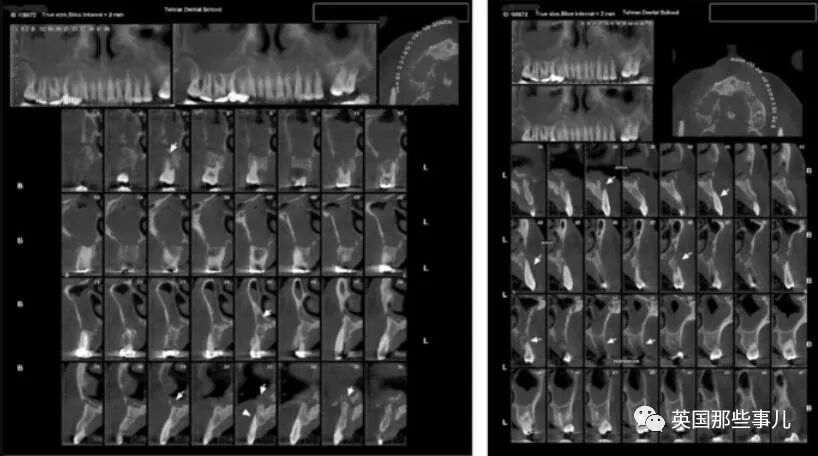

他再次被轉診到牙周病醫生處,醫生發現他血糖壹直比較高,出現多發性牙齦膿腫,兩側上頜竇都出現明顯的陰影,鼻底和上頜竇壁也出現穿孔。- 新聞來源於其它媒體,內容不代表本站立場!